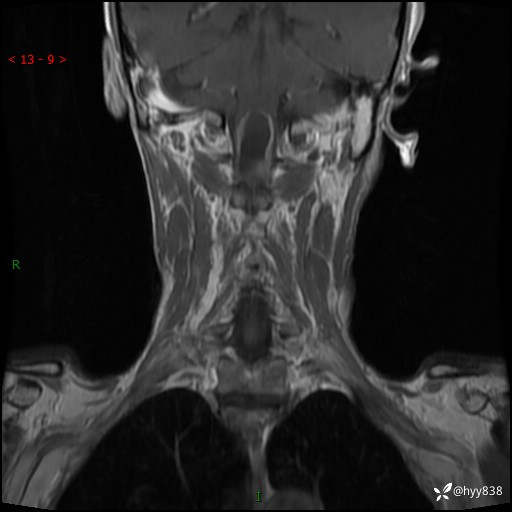

颈椎MRI平扫(sag T1WI+T2WI-fs+axi T2WI)